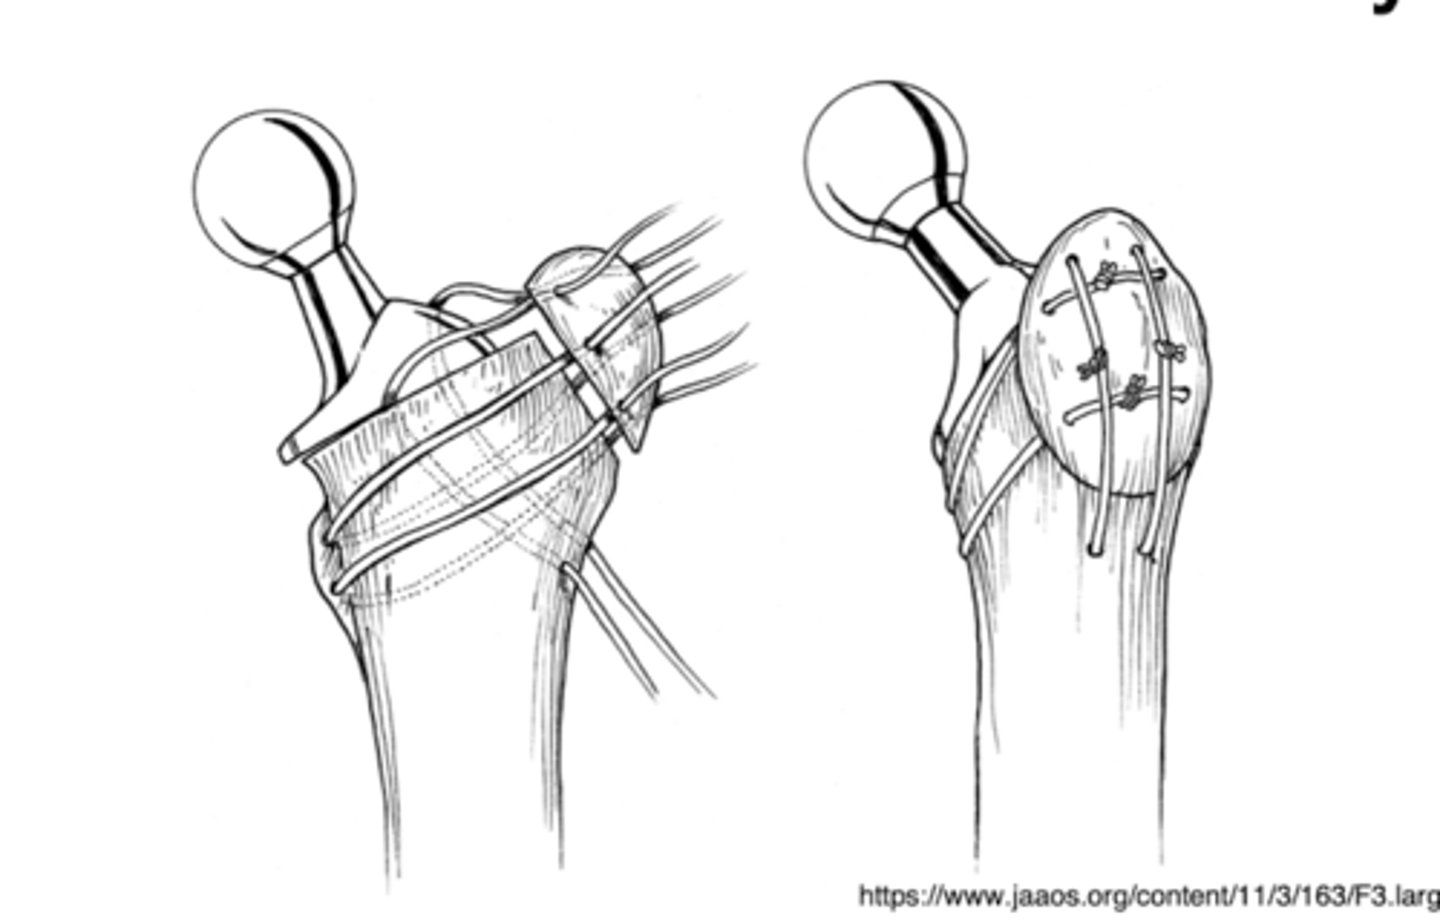

periacetabular osteotomy

used for hip dysplasia. break femur and pelvis, rotate them to provide greater joint angle

trochanteric osteotomy

used for THA revisions